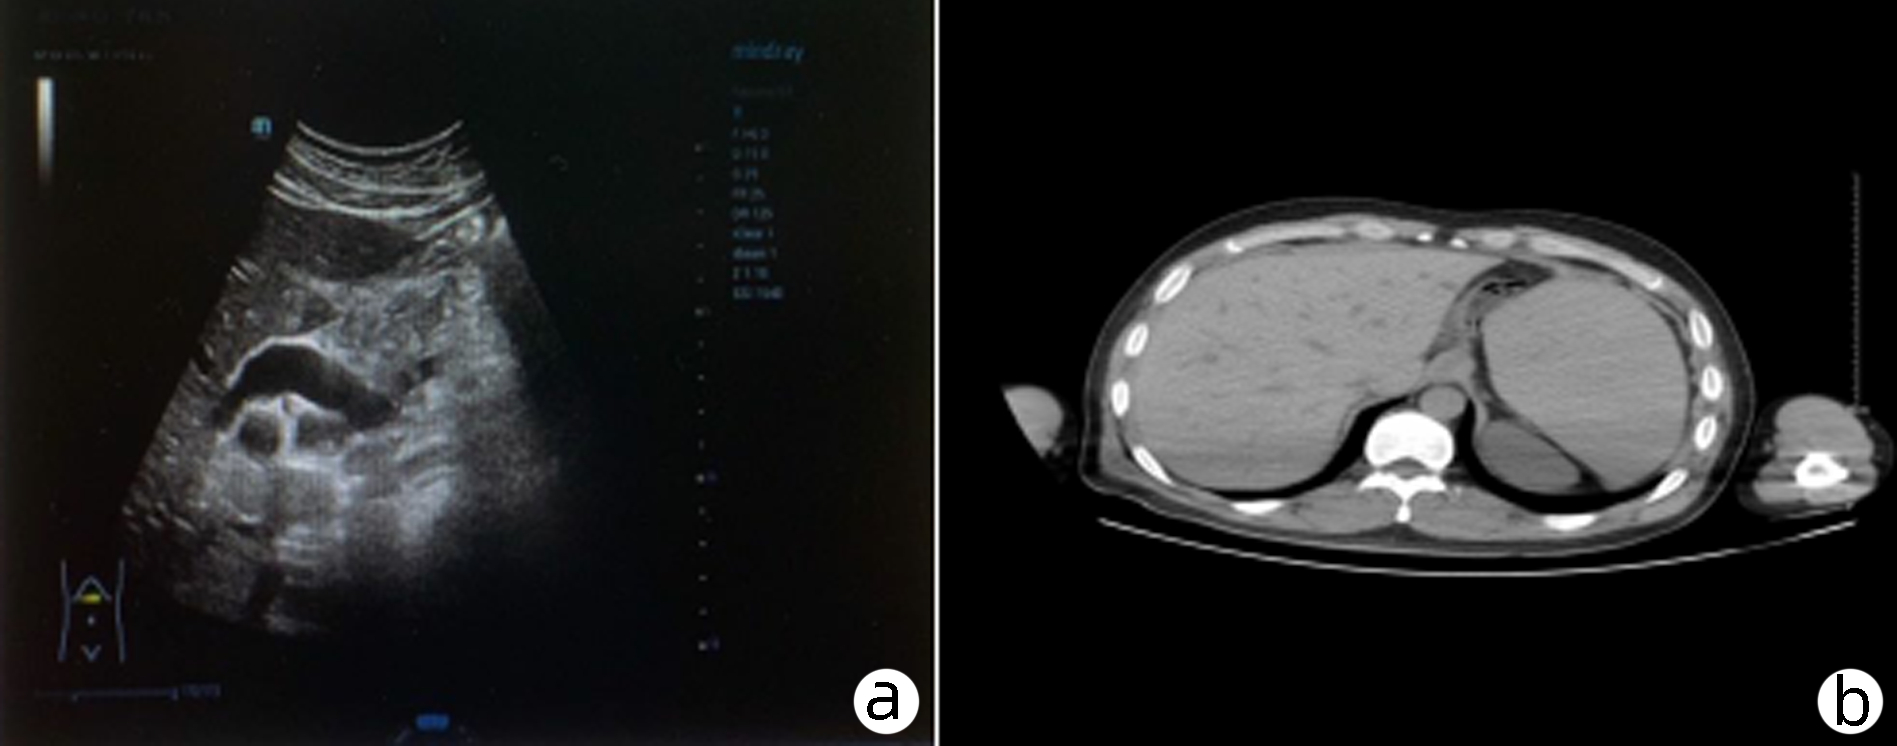

阿卜杜萨拉木·图尔荪麦麦提, 张云飞, 姚刚, 沙地克·阿帕尔, 吐尔洪江·吐逊, 温浩

2023, 39(8): 1922-1925. DOI: 10.3969/j.issn.1001-5256.2023.08.023

摘要(1461) HTML (312) PDF (2217KB)(118)

摘要:

遗传性球型红细胞增多症是一种人体红细胞膜缺陷遗传性溶血疾病,主要以贫血、黄疸、脾大为主要症状,因临床症状不典型,容易误诊漏诊,目前临床上总胆红素及直接胆红素极高病例较少见,国内外很少有报道,文本患者入院接受治疗时总胆红素高达1 686.01 μmol/L,直接胆红素高达1 166.6 μmol/L。经外科治疗该患者顺利出院,术后随访一般情况佳,生活质量高,本文总结了外科治疗遗传性球型红细胞增多症的相关诊疗经验。